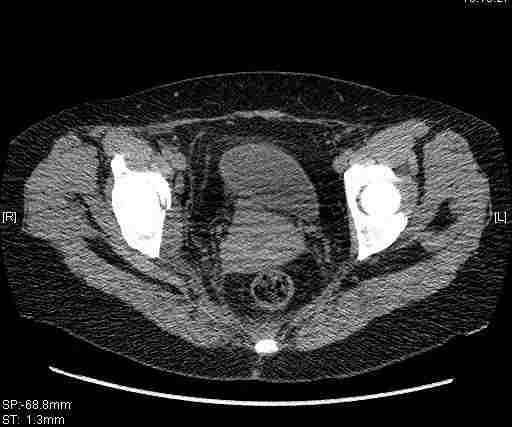

Женщина,58 лет, после ДТП 6 суток. Первично повреждение расценено как переломы ветвей лонной кости. После подтверждения повреждения вертлужной впадины,как чаще всего случается, вопрос встал о тактике. БОльшинство за консерватиное лечение.К сожалению кт у нас "во время" сломался. Прилагаю стандартные снимки вертлужки. У меня следующие вопросы к коллегам:1. Правильно ли рассценивать это повреждение как Т-образный перелом вертлужнй впадины?2. Можно ли добиться анатомической репозиции поверхности вертлужной впадины скелетным вытяжением в данном случае, если нет, что будет этому препятствовать?3. Если смещение останется таким как сейчас, через какое время появится необходимость эндопротезирования (по вашему опыту)?Спасибо.

Удалось сегодня вывести пациентку в соседнюю больницу, где есть кт. Срезы сделаны только горизонтальные.

|

Приветствую,Антон.Рункова рядом нет,но после полученных данных КТ,обсуждали совместно.Итог обсуждения-развернутый ответ дать не получится,т.к.срезы выбраны не информативные.Если ориентироваться на данные 3D,то ,ИМХО,можно лечить на вытяжении.